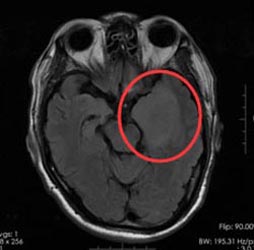

46岁的孙先生,半年前开始出现头疼、头晕症状,肢体活动正常,他觉得这是常有的小毛病,一直没有去医院。直到一周前,孙先生头痛症状加重,当地医院就诊,头部MRI提示左颞岛叶异常信号,考虑为低级别胶质瘤。

广东三九脑科医院进一步检查结果:1、左侧颞叶占位性病变;2、高血压病1级,高危组。

手术前